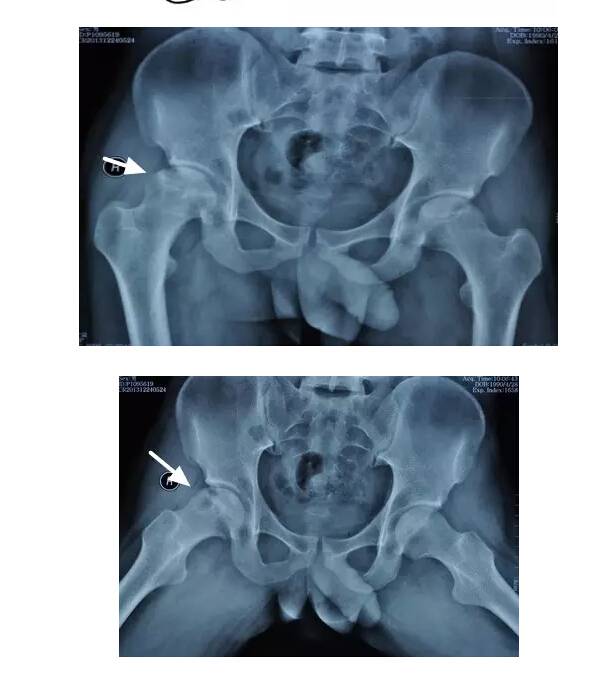

I期病人有髋部症状,X线片正常,磁共振出现异常

I期的患者在口服以上药物的同时,可以行股骨头坏死钻孔减压术,并且要定期复查,密切观察病情发展,尽量避免重体力劳动和爬山爬楼。